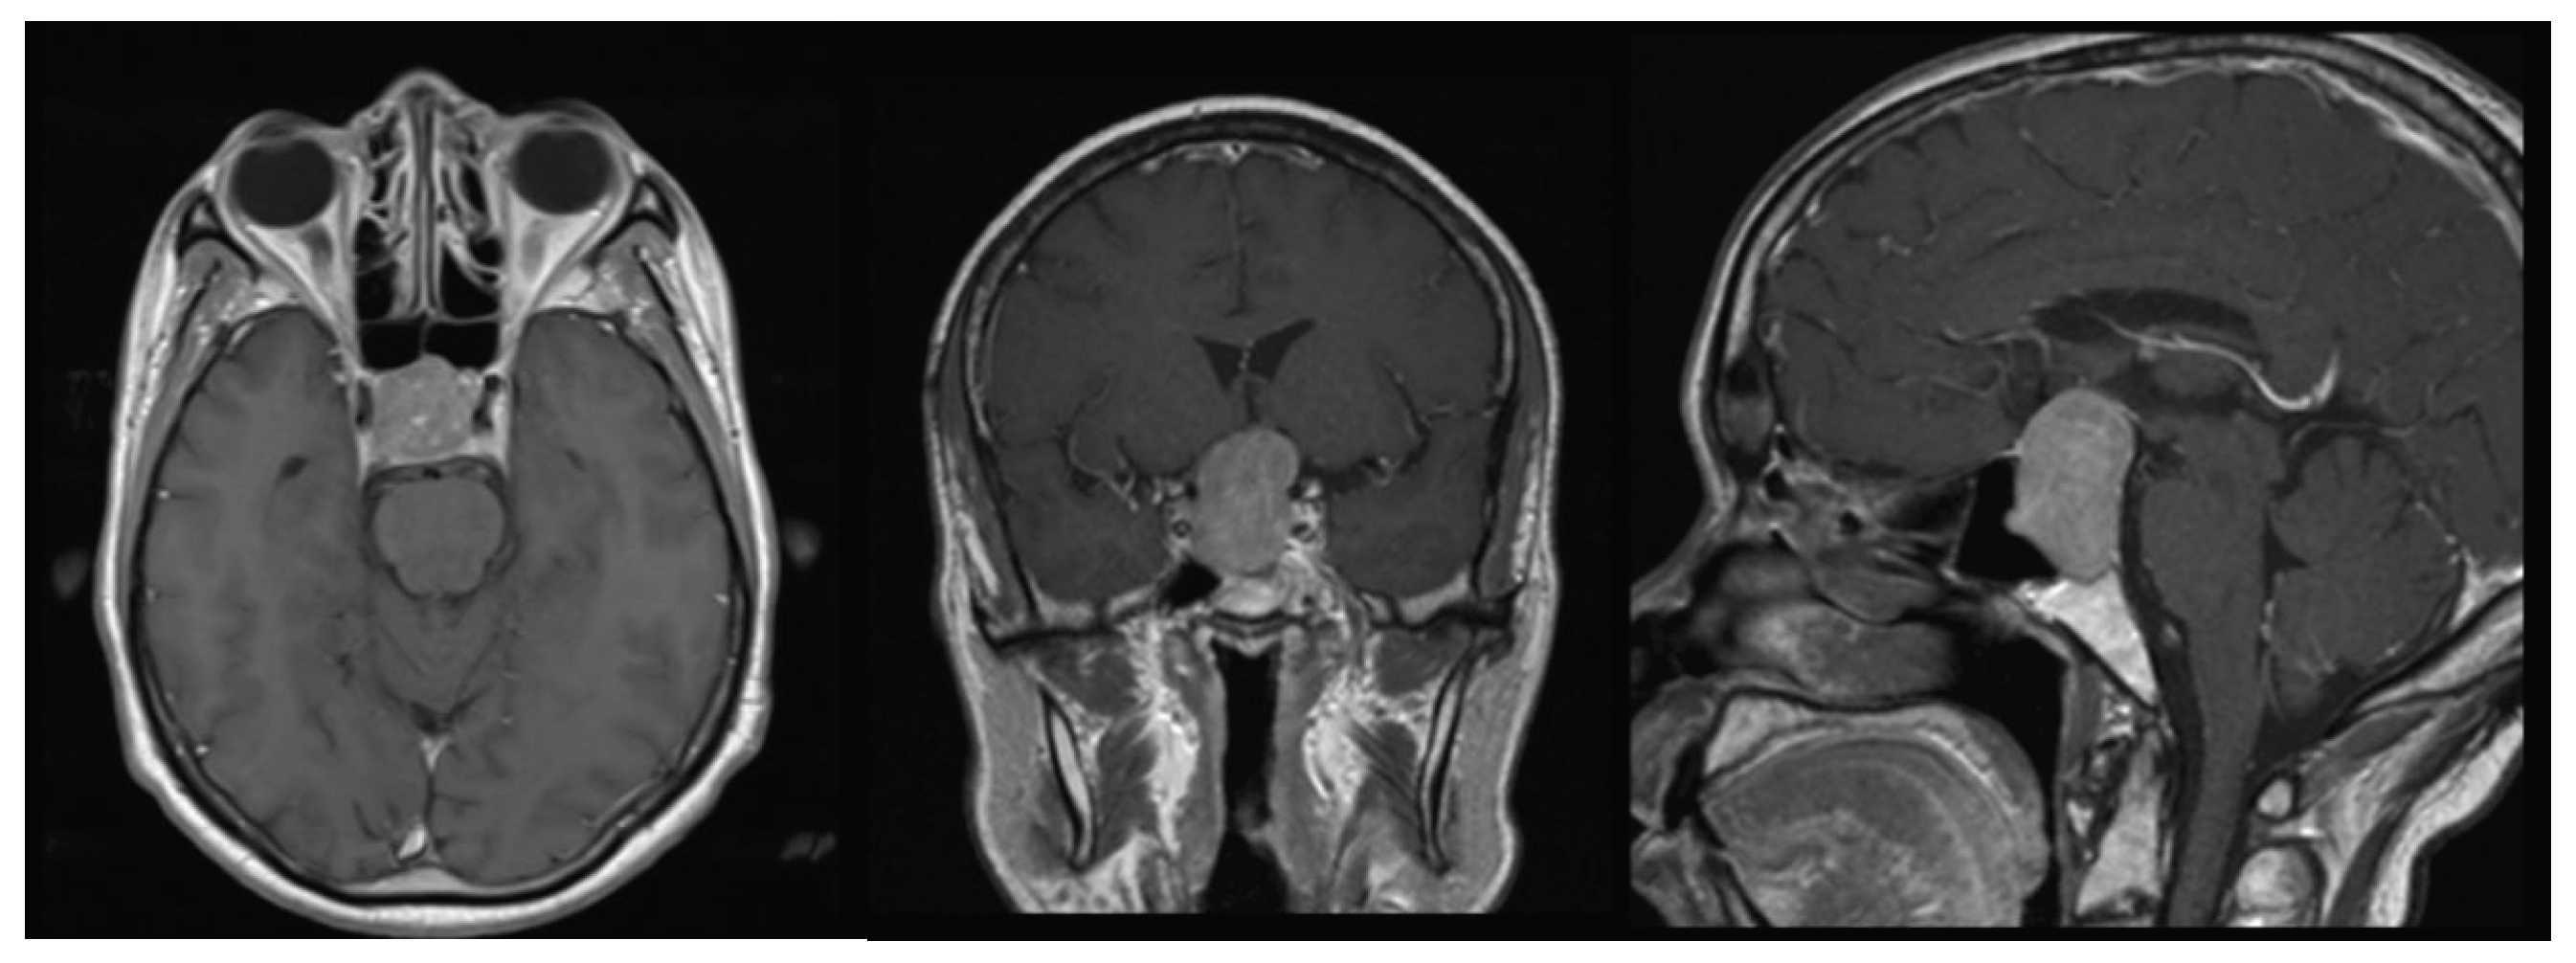

A 58-year-old woman presented with severe hyponatremia, headache, and bitemporal hemianopsia. As shown in Figure 1, preoperative MRI revealed midline pituitary macroadenoma extending suprasellarly, compressing the optic chiasm and not invading cavernous sinuous.

Figure 1. axial, sagittal and coronal MRI performed before surgery.